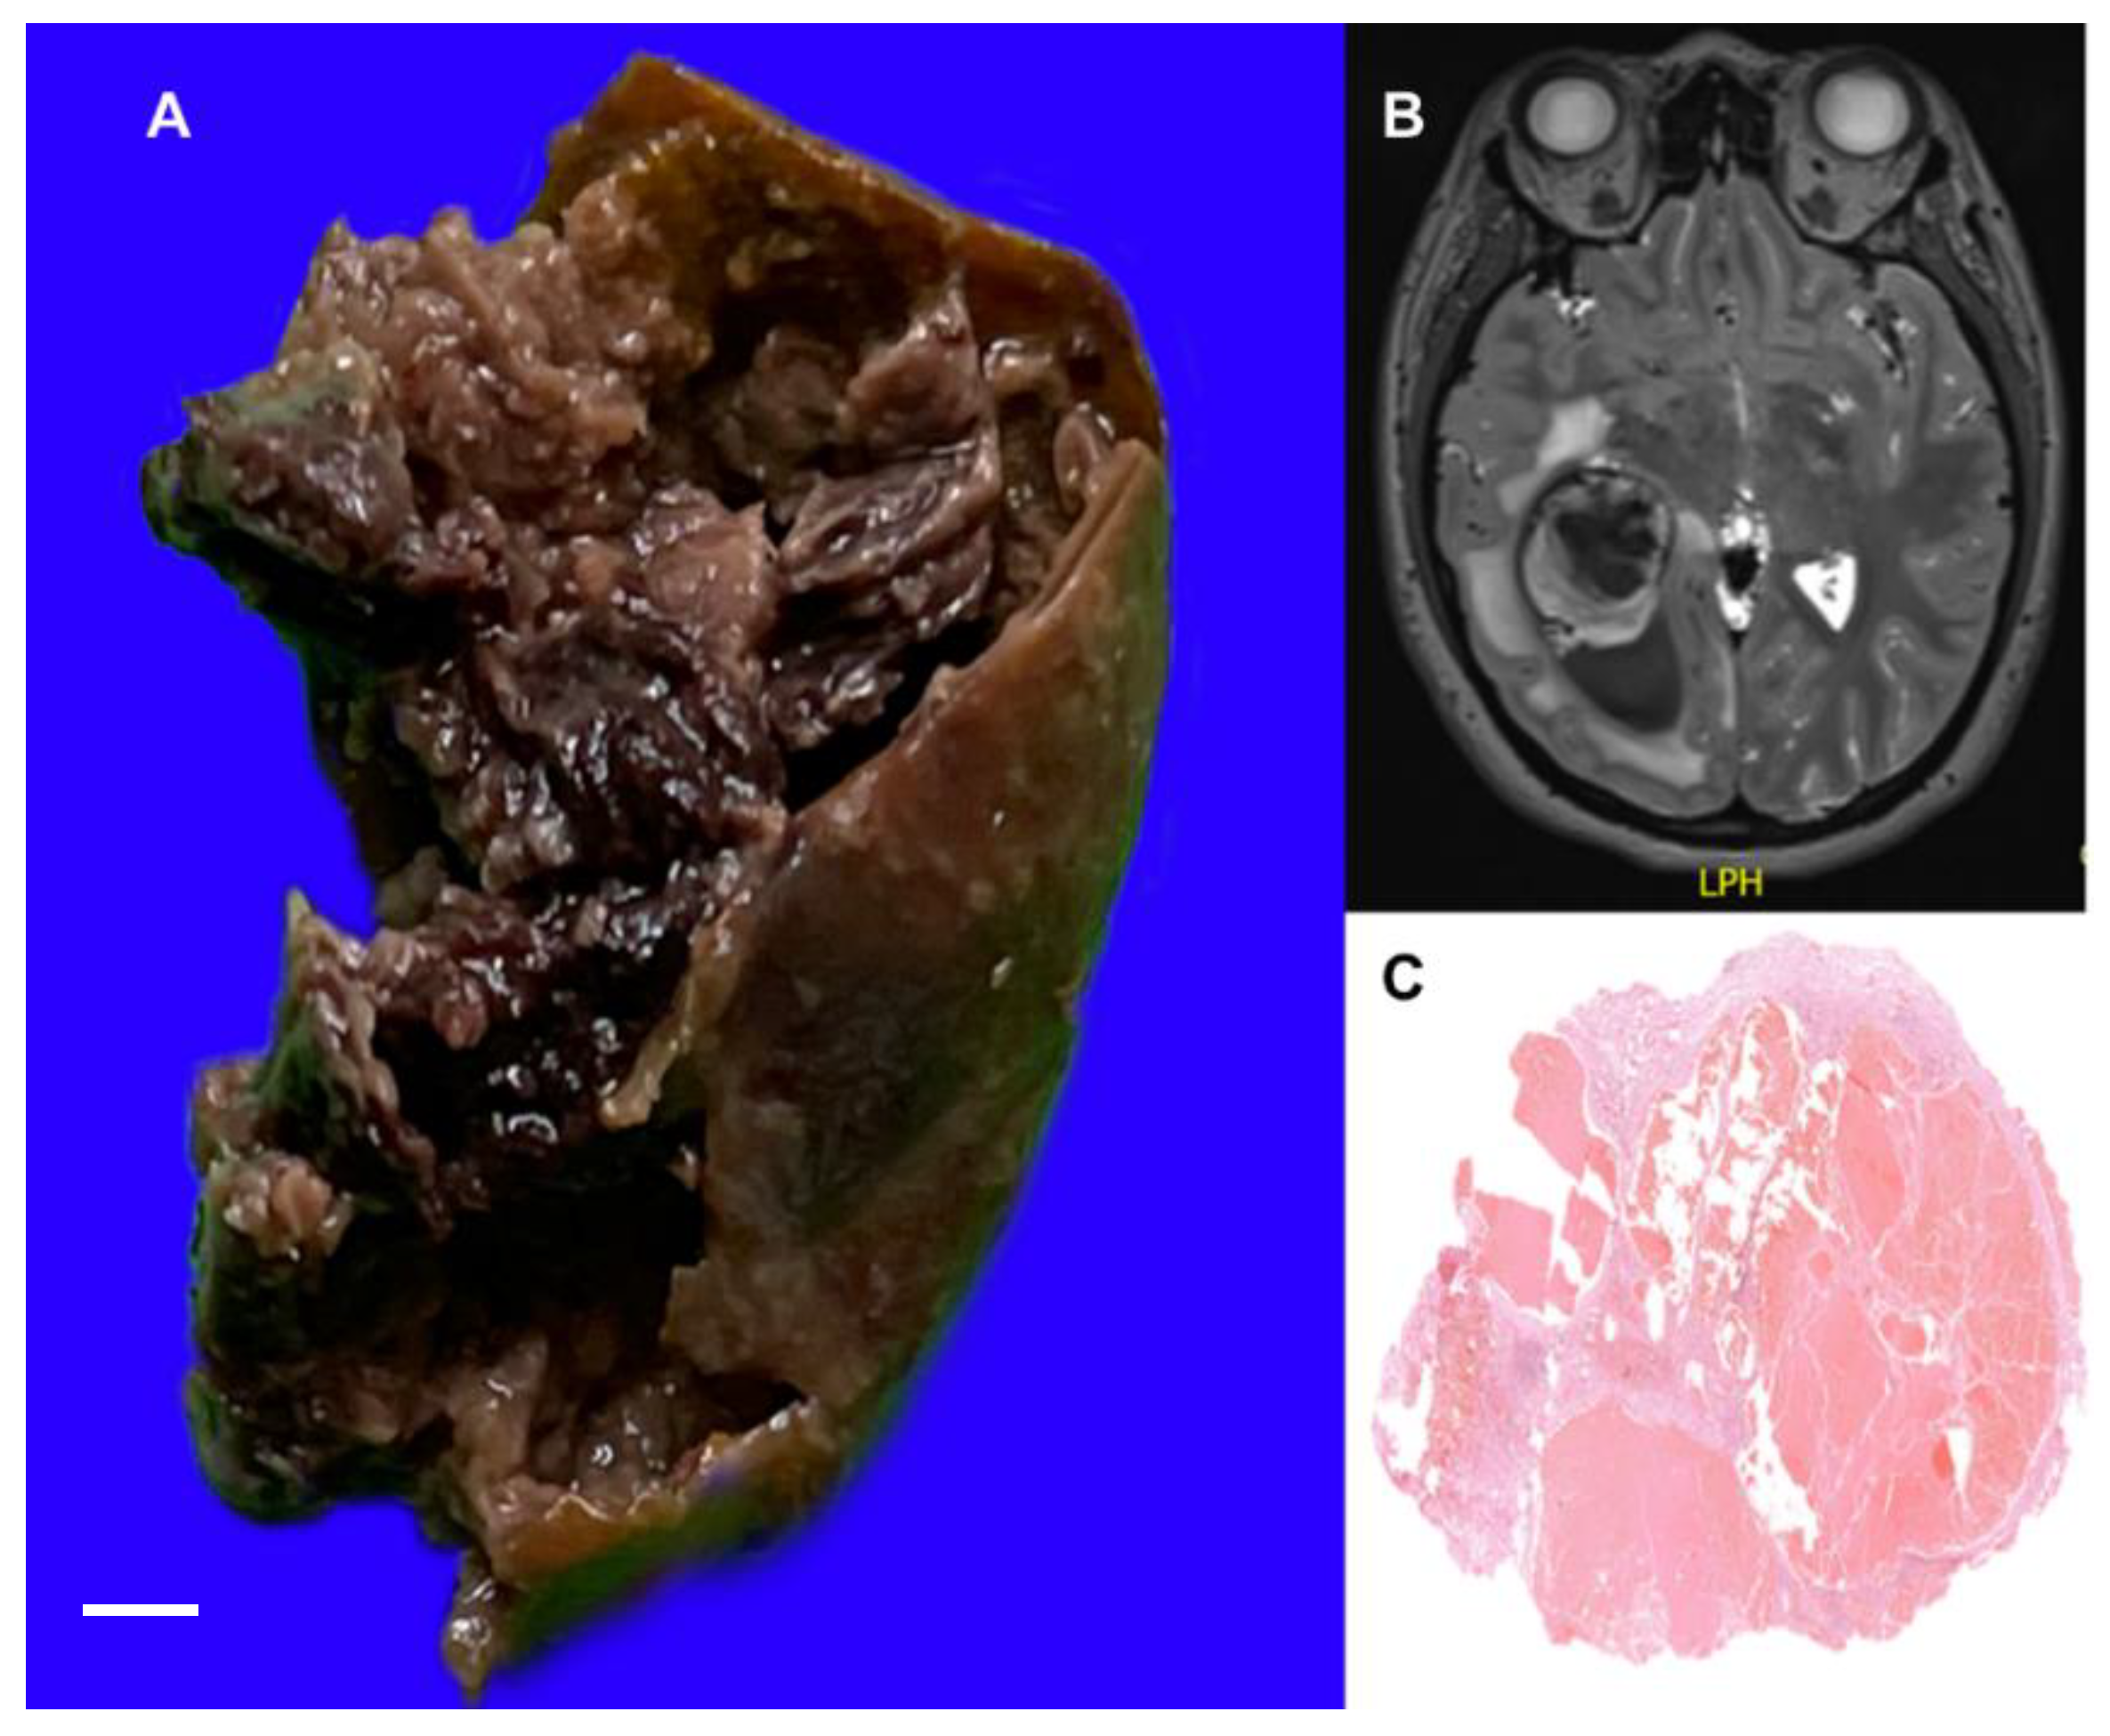

3.1.2. Brain Cavernous Angiomas

- Bokhari, M.R.; Al-Dhahir, M.A. Brain Cavernous Angiomas. In StatPearls; StatPearls Publishing: Treasure Island, FL, USA, 2022. [Google Scholar]

- Hassani, F.D.; Karekezi, C.; El Abbadi, N. Rare Case of Giant Pediatric Cavernous Angioma of the Temporal Lobe: A Case Report and Review of the Literature. Surg. Neurol. Int. 2020, 11, 7. [Google Scholar] [CrossRef] [PubMed]

- Mokin, M.; Agazzi, S.; Dawson, L.; Primiani, C.T. Neuroimaging of Cavernous Malformations. Curr. Pain Headache Rep. 2017, 21, 47. [Google Scholar] [CrossRef]